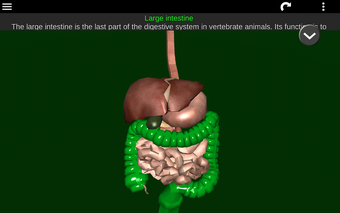

此应用程序显示人体器官的三维模型和所有器官的描述。

您可以触摸每个器官,如心脏、大脑、肺、生殖系统、肝脏、肠道、卵巢、睾丸、胃、肾脏等。

它对所有人都有用,甚至对学生也有用,因为每个解剖器官都以不同的颜色显示。

您可以使用该应用程序找出哪些是不同的身体器官以及它们的功能。